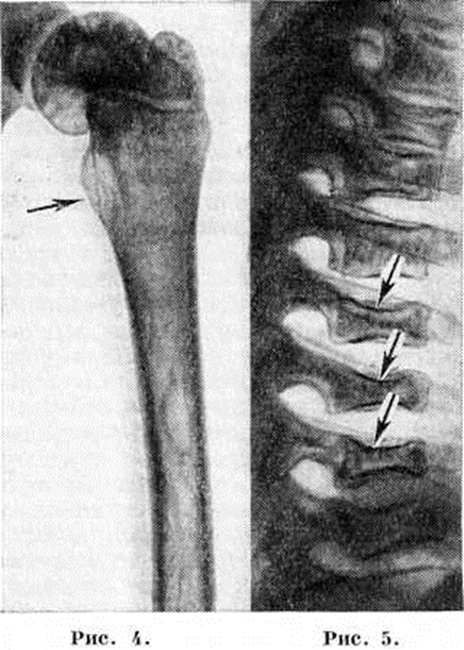

Некоторые авторы считают характерными признаками острой формы Гоше болезнь сочетание косоглазия, дистонии мышц конечностей и гиперэкстензии головы, деменции. Глазное дно обычно остаётся без изменений; у некоторых больных выявляется пигментный ретинит. Описанная неврологический симптоматика может быть ведущей в клинический, картине заболевания. Иногда ведущим в клинический, картине острой формы Гоше болезнь становится лёгочное поражение, обусловленное скоплением клеток Гоше в стенках альвеол. В этих случаях отмечается коклюшеподобный кашель, в мокроте можно найти клетки Гоше. Хронический форма протекает значительно доброкачественнее. В большинстве случаев она проявляется в юношеском возрасте или у взрослых. Физ. и психическое развитие больных, как правило, не страдает. Размеры селезёнки и печени увеличиваются постепенно. Обычно в процесс вовлекаются и лимфатических, узлы, преимущественно висцеральные. Изменения картины крови при хронический форме Гоше болезнь те же, что и при злокачественной форме: анемия, лейкопения, тромбоцитопения; однако выражены они значительно слабее. Геморрагический синдром длительное время проявляется склонностью к подкожным кровоизлияниям и непродолжительными носовыми кровотечениями. Иногда отмечается субфебрильная температура. Характерно появление жёлто-коричневой пигментации на открытых частях кожи, слизистых оболочках и на склерах. Часто возникают боли в костях, вызывающие затруднения при ходьбе. В ряде случаев костные поражения могут быть наиболее ранними симптомами и преобладать во всей клинический, картине болезни. Иногда костные изменения осложняются патологический переломами. У некоторых больных отмечается специфическое поражение лёгких и желудочно-кишечного тракта. При хронический форме Гоше болезнь неврологический нарушения обнаруживают значительно реже, чем при острой, и выражены они весьма незначительно (пирамидные симптомы, интенционный тремор, дисметрия, вегетативные нарушения проявляются гипергидрозом, тахикардией, лабильностью пульса). Ряд авторов выделяет третью форму Гоше болезнь, развивающуюся в юношеском возрасте или у взрослых и характеризующуюся преимущественным поражением центральная нервная система, но имеющую более мягкое течение, сходное с хронический формой. Рентгенологическая картинаРентгенологическое изменения обнаруживают в костной системе, лёгких и в редких случаях в желудочно-кишечного тракте, главным образом при хронический форме болезни. Наиболее часто изменения обнаруживают в длинных трубчатых костях и позвоночнике. Первое место по частоте поражения занимает дистальная половина бедра, где выявляют характерное веретенообразное или булавовидное вздутие кости (рисунок 2 и 3) с истончением коркового слоя, которое часто сочетается с грубо-ячеистой структурой, внутрикостными обызвествлениями, отдельными очагами деструкции и иногда с эностальным склерозом кости. Периостозы, как правило, не развиваются; иногда могут наблюдаться обширные краевые деструкции, сопровождающиеся периостозами. В головке бедренной кости образуются асептические некрозы по типу болезни Пертеса со свойственной данному заболеванию стадийностью процесса и исходами (смотри полный свод знаний Пертеса болезнь). Может наблюдаться утолщение шейки бедра (рисунок 4) с образованием coxa vara. Патологический переломы тел позвонков могут привести к клиновидной их деформации. Сохранность межпозвоночного диска позволяет исключить туберкулёзный характер поражения. В ряде случаев развивается множественное поражение тел позвонков, сопровождающееся уменьшением их высоты и приводящее к снижению роста больного — системная бревиплатиспондилия (рисунок 5). Изменения в органах грудной полости выявляются редко. В лёгких рентгенологически отмечают усиление интерстициального рисунка с точечными очажками уплотнения, иногда в сочетании с увеличением внутригрудных лимф, узлов. Ещё более редки поражения желудочно-кишечного тракта, характеризующиеся появлением в желудке дефектов наполнения. Диагноз ставят на основании клинический, картины, данных лабораторных и рентгенологических исследований. Основным критерием для диагностики Гоше болезнь является обнаружение в пунктате селезёнки, костного мозга или печени клеток Гоше. В пунктате наряду с отдельно лежащими клетками могут встречаться и синцитиальные образования из них. Описаны единичные случаи вымывания клеток Гоше в периферическую кровь и выявления их методом лейкоконцентрации (смотри полный свод знаний Лейкоциты). Гоше болезнь можно диагностировать биохимический методом, выявляя дефицит фермента глюкоцереброзидазы в лейкоцитах периферической крови, в культуре фибробластов кожи и в культуре клеток из амниотической жидкости. У больных с острой формой Гоше болезнь содержание фермента составляет 5—10% нормы, у больных с хронический формой — 40—60%. Для диагностики Гоше болезнь определяют также содержание глюкоцереброзидов в осадке мочи больного или в биопсийном материале, например, в печёночной ткани. Содержание этих глюколипидов повышено. В сыворотке крови больного обнаруживается избыток кислой фосфатазы, выявляется гиперкальциемия. Исследование культуры клеток из амниотической жидкости позволяет выявлять носителей дефицита фермента глюкоцереброзидазы в пренатальном периоде жизни. Лечение острой формы симптоматическое. Основной метод лечения хронический формы Гоше болезнь — спленэктомия (смотри полный свод знаний). Попытка терапии отдельных форм сфинголипидозов, к которым относится Гоше болезнь, введением в плазму больных недостающих ферментов пока не дала надёжных результатов. Прогноз при острой форме Гоше болезнь неблагоприятный; смерть наступает на 1—2-м году жизни. Прогноз хронический формы, как правило, благоприятный. Профилактика. В случае рождения в семье ребёнка со злокачественной формой болезни при последующих беременностях матери больного показано исследование амниотической жидкости плода. При диагностике Гоше болезнь у 11 — 17-недельного плода показано прерывание беременности. Специфической профилактики нет. Смотри также Липоидозы, Сфинголипидозы.